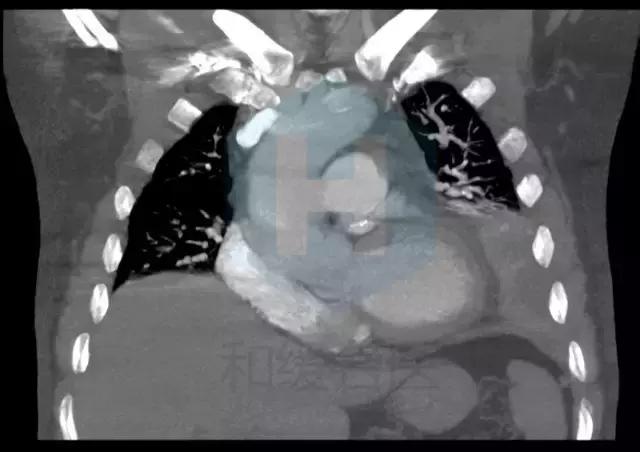

从CT来看,是比较典型的肺栓塞的表现,应该做肺动脉造影检查。

患者有胸痛,胸闷,1型呼吸衰竭,胸部影像示左下肺为“三角形”肺实变影伴胸腔积液,高度怀疑存在肺栓塞,建议行CTPA检查和肺核素通气/灌注现象检查。同时需排除肺栓塞原因,如肿瘤,自身免疫性疾病等。肺栓塞也会有黄疸和溶血表现。 胸痛特点和表现不符合心绞痛,左侧胸腔积液与左侧肺部病变有关。 患者黄疸考虑为溶血性黄疸,应行查找溶血原因,此外,血红蛋白有降落,便潜血阳性,有同时伴有失血可能,建议查血网织红细胞计数评价贫血情况,应行胃肠镜检查以明确消化道出血原因。 目前低价血症原因考虑不除外副肿瘤综合症可能,关注纠正电解质紊乱。 可视医院条件,建议安排下一步检查:胸部增强CT及CTPA,或肺通气/灌注检查,下肢及深静脉超声,血肿瘤标志物,血网织红细胞计数,自身免疫抗体(ANA,ENA,ANCA)等,胃肠镜检查。 由于目前有消化道出血风险,暂不建议抗凝治疗。密切视察。